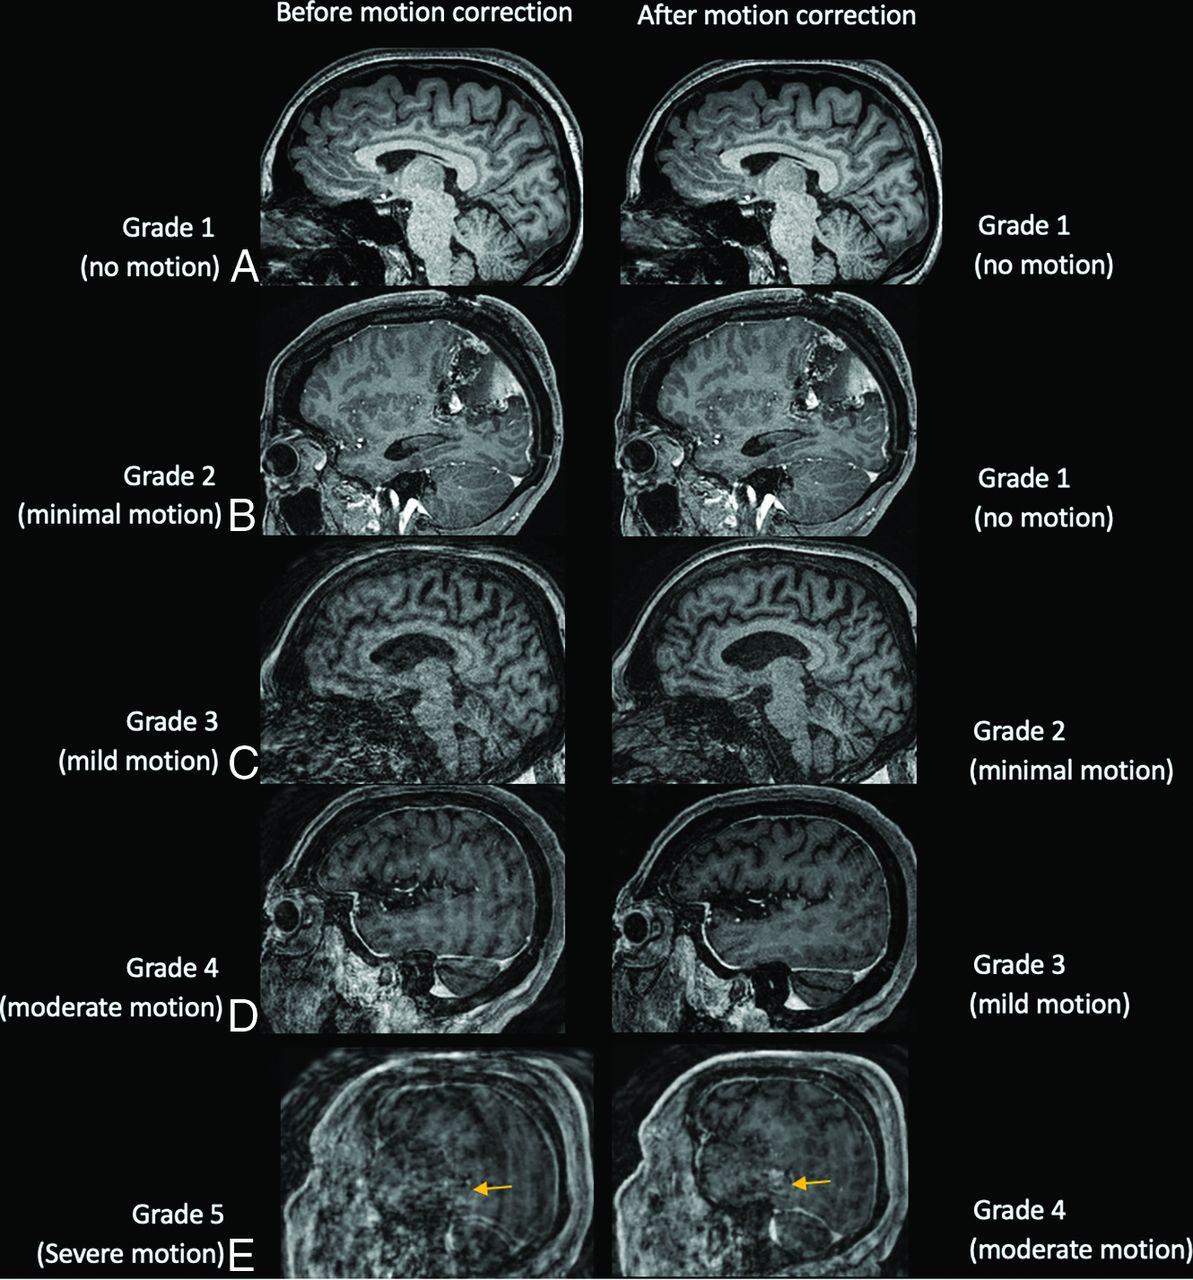

Two neuroradiologists (M.L. and J.F. with 3 and 5 years of experience, respectively) performed independent blinded reviews of unlabeled MPRAGE images without and with SAMER motion correction. The order of the study and the type of study (baseline-versus-SAMER motion-corrected images) were randomized by A.T. for the reviewing neuroradiologists. Cases with any discrepant grades were adjudicated independently by a third blinded senior neuroradiologist (J.C.) with >10 years of experience. A previously established 5-point motion scale was used for grading (Fig 1).1 Grade 1 indicates the absence of detectable motion artifacts; grade 2 indicates minimal motion with barely detectable motion artifacts and a negligible effect on image quality and diagnosis; grade 3 indicates mild motion with noticeable motion artifacts that likely do not have diagnostic consequences; grade 4 indicates moderate motion artifacts that degrade and possibly obscure underlying pathology; and grade 5 indicates severe motion artifacts that distort anatomy and obscure underlying pathology. Grades 1, 2, and 3 were considered diagnostic quality with regard to motion artifacts, whereas grades 4 and 5 were considered nondiagnostic, as defined in the original article by Andre et al.1 The motion grade improvement was defined as the precorrection motion grade minus the postcorrection grade.

Motion scale used for the clinical quantification of motion artifacts along with representative cases before motion correction. The arrows point to areas of image blurring due to motion artifacta.

Among the 5 cases with baseline no motion (motion grade 1), there was no change in the motion grade after SAMER motion correction. Of the 46 cases with minimal motion (motion grade 2), most cases (78%) showed no change in motion grade, while motion artifacts worsened by 1 grade in 8 cases (17%) and improved in 2 cases (4%). The Online Supplemental Data show an example of a case with minimal motion (grade 2) at baseline that worsened to mild motion (grade 3) on SAMER motion correction. Note that the degree of motion in the SAMER motion-corrected images is still quite small and did not compromise the diagnostic quality of the image. In 30 cases with baseline mild motion (motion grade 3), there was no change in the motion grade for 19 cases (63%) and improvement in 11 cases (37%). Representative side-by-side comparison of baseline and SAMER motion-corrected images are provided in Fig 2.

Sagittal T1 MPRAGE images illustrating examples of cases with motion artifacts (grades I–5) for which SAMER reconstruction improved motion by 1 grade. A, A 23-year-old woman with a normal brain. B, Postoperative findings from resection of a left parietal lobe tumor in a 59-year-old woman with a history of anaplastic oligodendroglioma. C, Diffuse parenchymal volume loss with disproportionate involvement of the frontal and parietal lobes and, to a lesser extent, the left temporal lobe in a 59-year-old man with history of cognitive impairment. D, An 83-year-old woman with history of chronic cerebral small-vessel disease. E, Expected postoperative changes and enhancement from left temporal parietal craniotomy (arrows) are demonstrated in a 63-year-old man with history of glioblastoma.